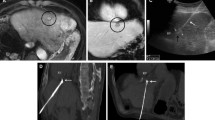

Representative cases of subcapsular HCCs for which no indirect puncture path was feasible because of the location or exophytic growth of the tumor. A CT images of a lateral subcapsular HCC with no possibility of an indirect puncture path. B T2 weighted-MR images showing an anterior and exophytic left lobe subcapsular HCC with no possibility of an indirect puncture path

Radiofrequency energy was supplied by a 3 × 2-channel 250-W, 470-kHz radiofrequency generator (CelonLabPower®; Olympus-Celon, Teltow, Germany). Two to six internally cooled 30–40-mm active 15-G electrodes were used, depending on the size and location of the tumors. In this setting, 2 to 4 applicators were usually used to treat tumors < 3 cm and 4 to 6 probes for HCCs between 3 and 5 cm. As previously detailed, the electrodes were inserted using free-hand technique, in compliance with the no-touch concept, with an objective of at least 5-mm margins around the tumor [17]. If necessary, the number of applicators was adjusted according to per-procedural requirements regarding proximity of large vessels or neighboring critical structures. Three electrode insertion strategies were employed to achieve no-touch tumor ablation (Fig. 3) [21]:

Illustrations of electrode implantation strategies. A Standard no-touch strategy. a CT images of a lateral subcapsular HCC treated with the implantation of four electrodes around the tumor in a parallel course. Continuous lines represent electrodes in front of the plan whereas discontinuous lines represent electrodes behind the plan. b. CT images at 1 month showing complete ablation. B Retro-nodular converging no-touch strategy. a CT images of an anterior subcapsular HCC treated with the implantation of four electrodes around the tumor in a retro-nodular converging course. Continuous lines represent electrodes in front of the plan whereas discontinuous lines represent electrodes behind the plan b CT images at 1 month showing complete ablation. Note that the preexisting small amount peri-hepatic ascites slightly increased at 1 month. B. No-touch cutting strategy. a Pre-therapeutic contrast-enhanced T1 weighted-MR images showing an anterior left lobe subcapsular HCC. White lines represent the electrodes. b Three-dimensional volume rendering reconstruction of post-procedural CT showing the ablation zone with a representation of the targeted tumor (circle) treated with the implantation of three electrodes according to a cutting strategy. c Axial and coronal CT images at 1 month showing complete ablation

a) the standard no-touch strategy, consisting in the parallel insertion of electrodes into the non-tumorous liver parenchyma around the tumor, with a maximum distance between adjacent probes of approximately 3 cm; b) the retro-nodular converging no-touch strategy, consisting in the convergent insertion of electrodes into the non-tumorous liver parenchyma, but around the tumor toward its hilar side (mainly used for exophytic tumors and those > 3 cm); c) the no-touch cutting strategy, used for peripheral nodules attached to the right or left lobe by a thin band of non-tumorous liver parenchyma. In this parenchyma band, the electrodes were here inserted in parallel (with a maximum distance of 3 cm between adjacent probes) to achieve complete ablation and wide ablative margins by means of the total upstream vascular deprivation of the tumor.

Forty-seven tumors (79.7%) were treated using a standard no-touch electrode implantation strategy, seven (11.8%) according to a no-touch retro-nodular converging approach and five (8.5%) with a cutting no-touch ablation technique. The median number of electrodes used was 3 [range 2–6], the median energy delivered was 91.5 kJ [range 22–276] and median radiofrequency application time was 24 min [range 5–60].